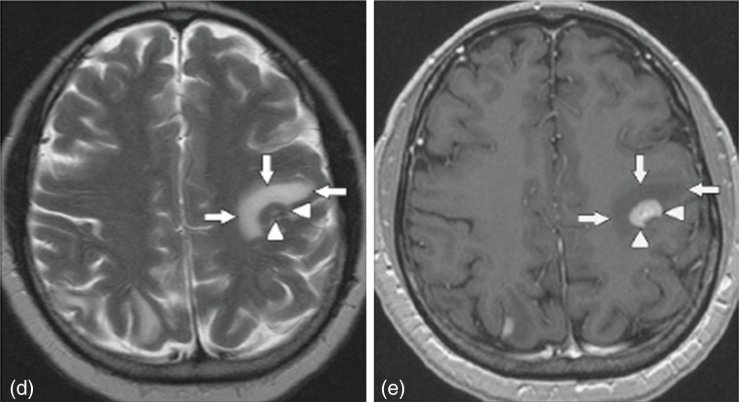

Методом вибору для діагностики метастатичних пухлин мозку є магнітно-резонансна томографія головного мозку з контрастуванням. Контрастна МРТ дозволяє виявити пухлинні вузли навіть невеликого розміру, оцінити їх локалізацію, кількість та ступінь впливу на навколишні мозкові структури.

Комп’ютерна томографія використовується як швидкий метод первинної оцінки стану мозку, особливо в ургентних ситуаціях. КТ дозволяє швидко виявити об’ємні утворення, набряк мозку або внутрішньочерепні крововиливи.